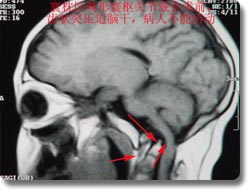

开展了脑内各部位肿瘤的显微手术治疗,尤其是经口鼻蝶入路作垂体瘤切除术、听神经瘤、斜坡脊索瘤、脑膜瘤、天幕、岩尖、鞍结节、海绵窦、脑膜瘤,颅鼻沟通瘤、跨前颅凹、中颅凹沟通瘤、跨后颅凹中颅凹沟通瘤、脑干肿瘤等多种疑难复杂的颅底肿瘤的显微手术治疗,手术成功率、肿瘤全切率、颅神经的保全率等均处于国内先进水平。并开展了寰枕区畸形寰枢关节脱位经口斜坡和切除等多种高难度手术,确立了神经外科在颅底手术领域的国内领先地位。颅底外科中经口、上颌骨劈开入路进行下斜坡、颅颈联合区的手术达到国际水平。 |